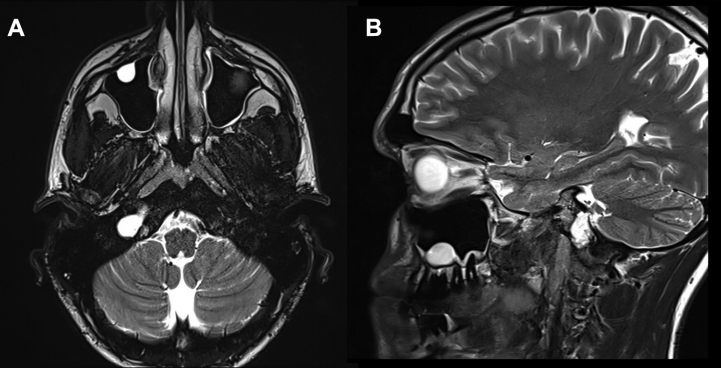

23岁法国小伙Lucas因右侧舌下麻痹和舌萎缩就诊,发现以颈静脉结节为中心的T2高信号和溶骨性病变(图1A和B)。

▼图1.术前MR显示以右颈静脉结节为中心病变,位于颈静脉孔内侧,考虑软骨肉瘤可能。

▼图2,术后MR证实软骨肉瘤完全切除。